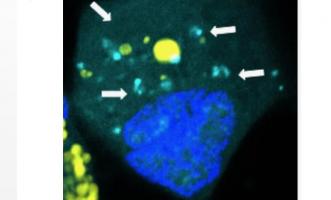

CANCER du CERVEAU : Injecter du code génétique nanométrique pour réparer les cellules

Actualité publiée le 06/08/2018ÉPILEPSIE : Boucher les fuites de la barrière hémato-encéphalique